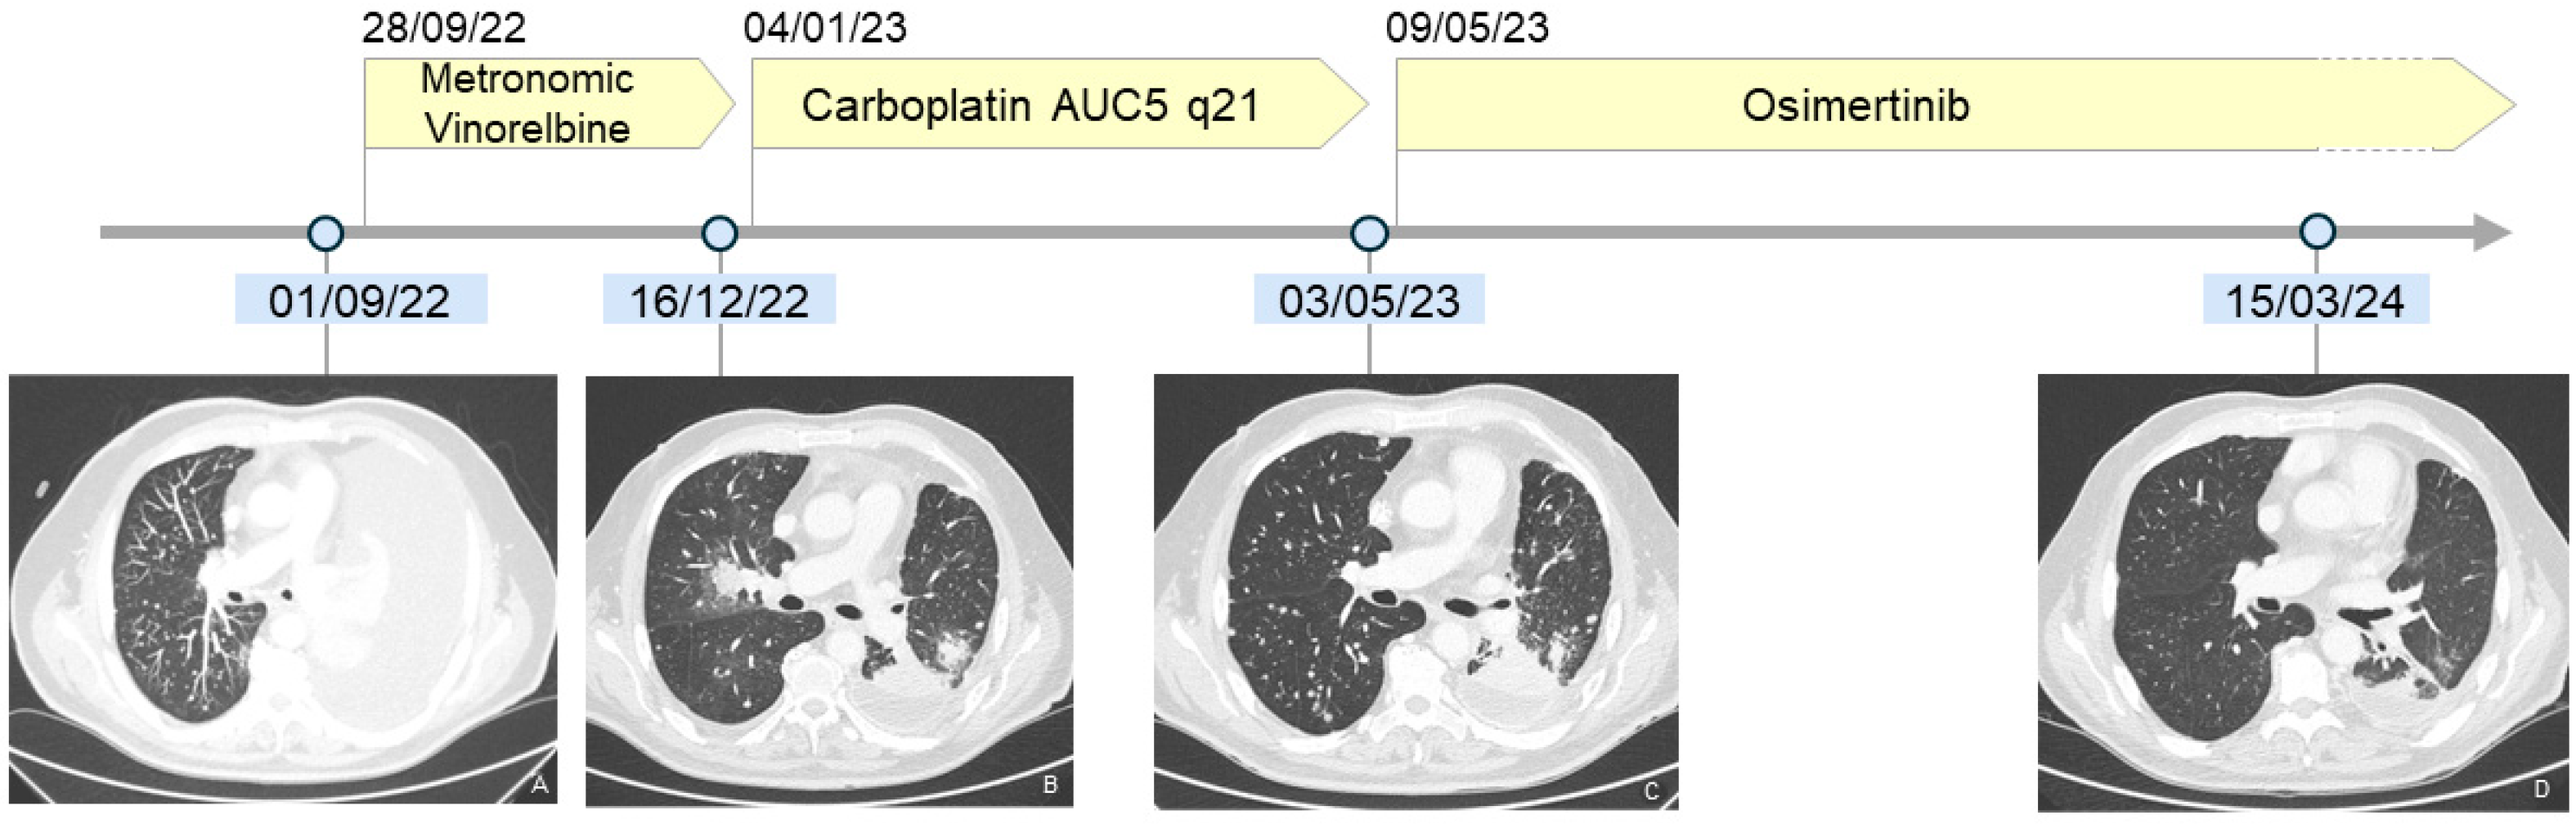

2. Case Description